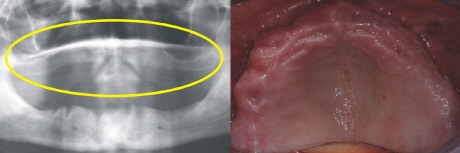

Ausgangssituation

Der zahnlose Unterkiefer rechts im Bild bietet keinen Halt mehr für eine Prothese. Links zeigt sich der zahnlose Knochenabschnitt im Röntgenbild (gelber Kreis).